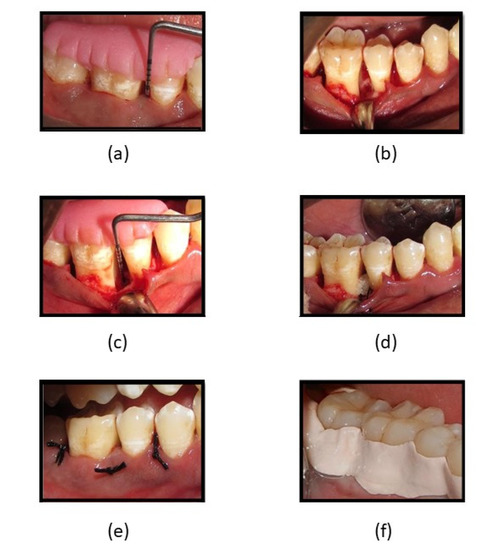

Surgical procedure (Figure 6)—Before the surgical procedure, the defect site was anesthetized by administering 2% lignocaine and an epinephrine concentration of 1:80,000, following which sulcular incisions were made on the buccal and lingual aspects of the involved sites and full-thickness mucoperiosteal flaps were raised. Area-specific curettes and ultrasonic scalers were used for thorough debridement, after which, the defect site in participants allocated to Group 1 was filled with fucoidan containing chitosan hydrogel as a bone regenerative material, and Group 2 had CGF for bone regeneration. Simple interrupted sutures were placed to achieve primary wound closure followed by the placement of periodontal dressing.

Figure 6. (a) PPD and CAL measuring 8-mm; (b) flap reflection, debridement, and surgical procedure of intra-bony defect; (c) intra-surgical measurement of intra-bony defect CEJ to depth of the bony defect; (d) fucoidan-chitosan gel placed into intra-bony site; (e) sutures placed and intra-bony defect covered by flap; (f) periodontal pack placed.